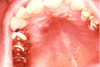

Extrinsic antigenic sources such as drugs have been identified as agents responsible for oral lichen planus (OLP)-like lesions. Drugs such as NSAIDs and ACE inhibitors can act as haptens and alter the antigenicity of epithelial self-antigens. OLP that can be traced to an extrinsic cause is more properly termed a lichenoid reaction.8,13-16 Oral lichenoid lesions most often affect the buccal mucosa (Figure 12 and Figure 13), gingivae, the lateral border of the tongue and may be “reticular,” erythematous, or atrophic.

Figure 12. Lichenoid stomatitis in a patient with rheumatoid arthritis taking ibuprofen.

Figure 12

Figure 13. Lichenoid stomatitis in a patient with rheumatoid arthritis taking ibuprofen.

Figure 13